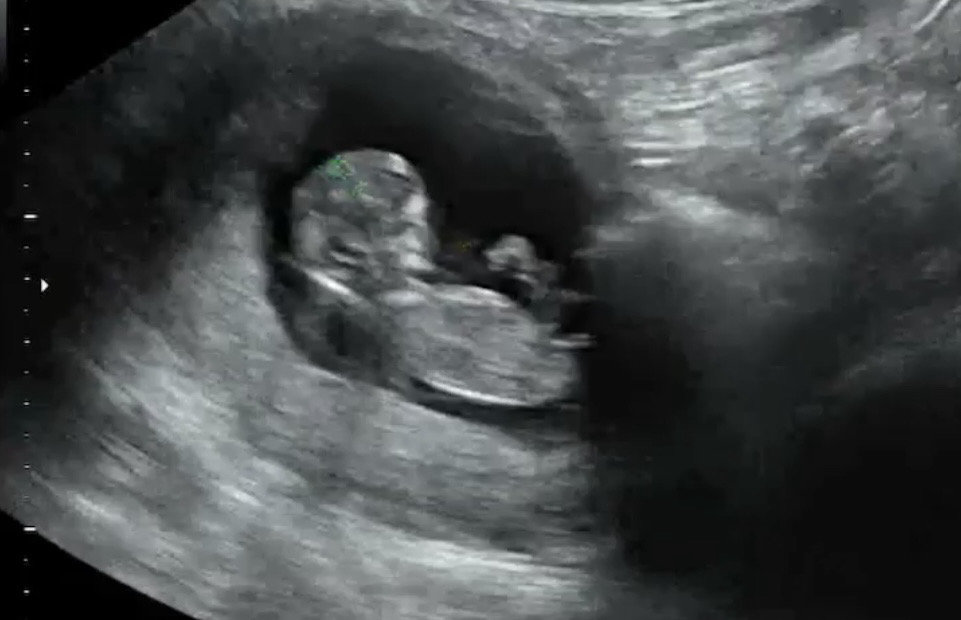

11주 4일 아가 각도법 부탁드려요🙏

이사진으로 판단할 수 있을까요..?

아들같은데 12주는 넘어야 좀 더 정확해요~!